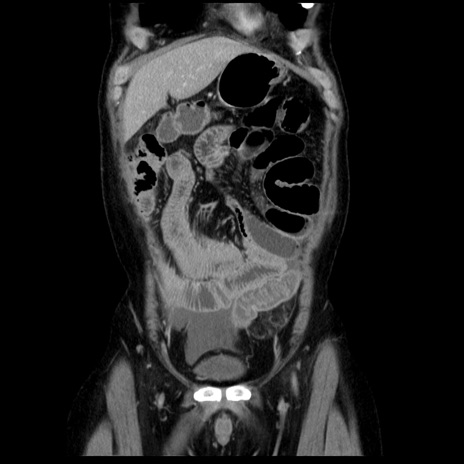

症例29(冠状断像)

【症例】40歳代男性

【現病歴】2日前から胃痛あり。徐々に周期的な激痛に変化した。本日になっても激痛があるため受診。

【身体所見】意識清明、BT 38-39℃台あり、腹部:膨満、やや硬、右下腹部に圧痛あり。

【データ】WBC 8500、CRP 23.26